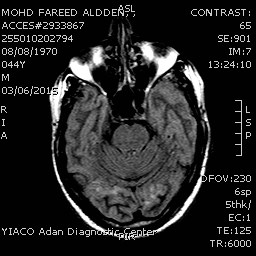

Bilateral

occipital areas of altered signal with faint hyper intensity on Flair images

cortical and sub cortical.

Abnormal

enhancement in the previously mentioned areas with abnormal meningeal

enhancement.